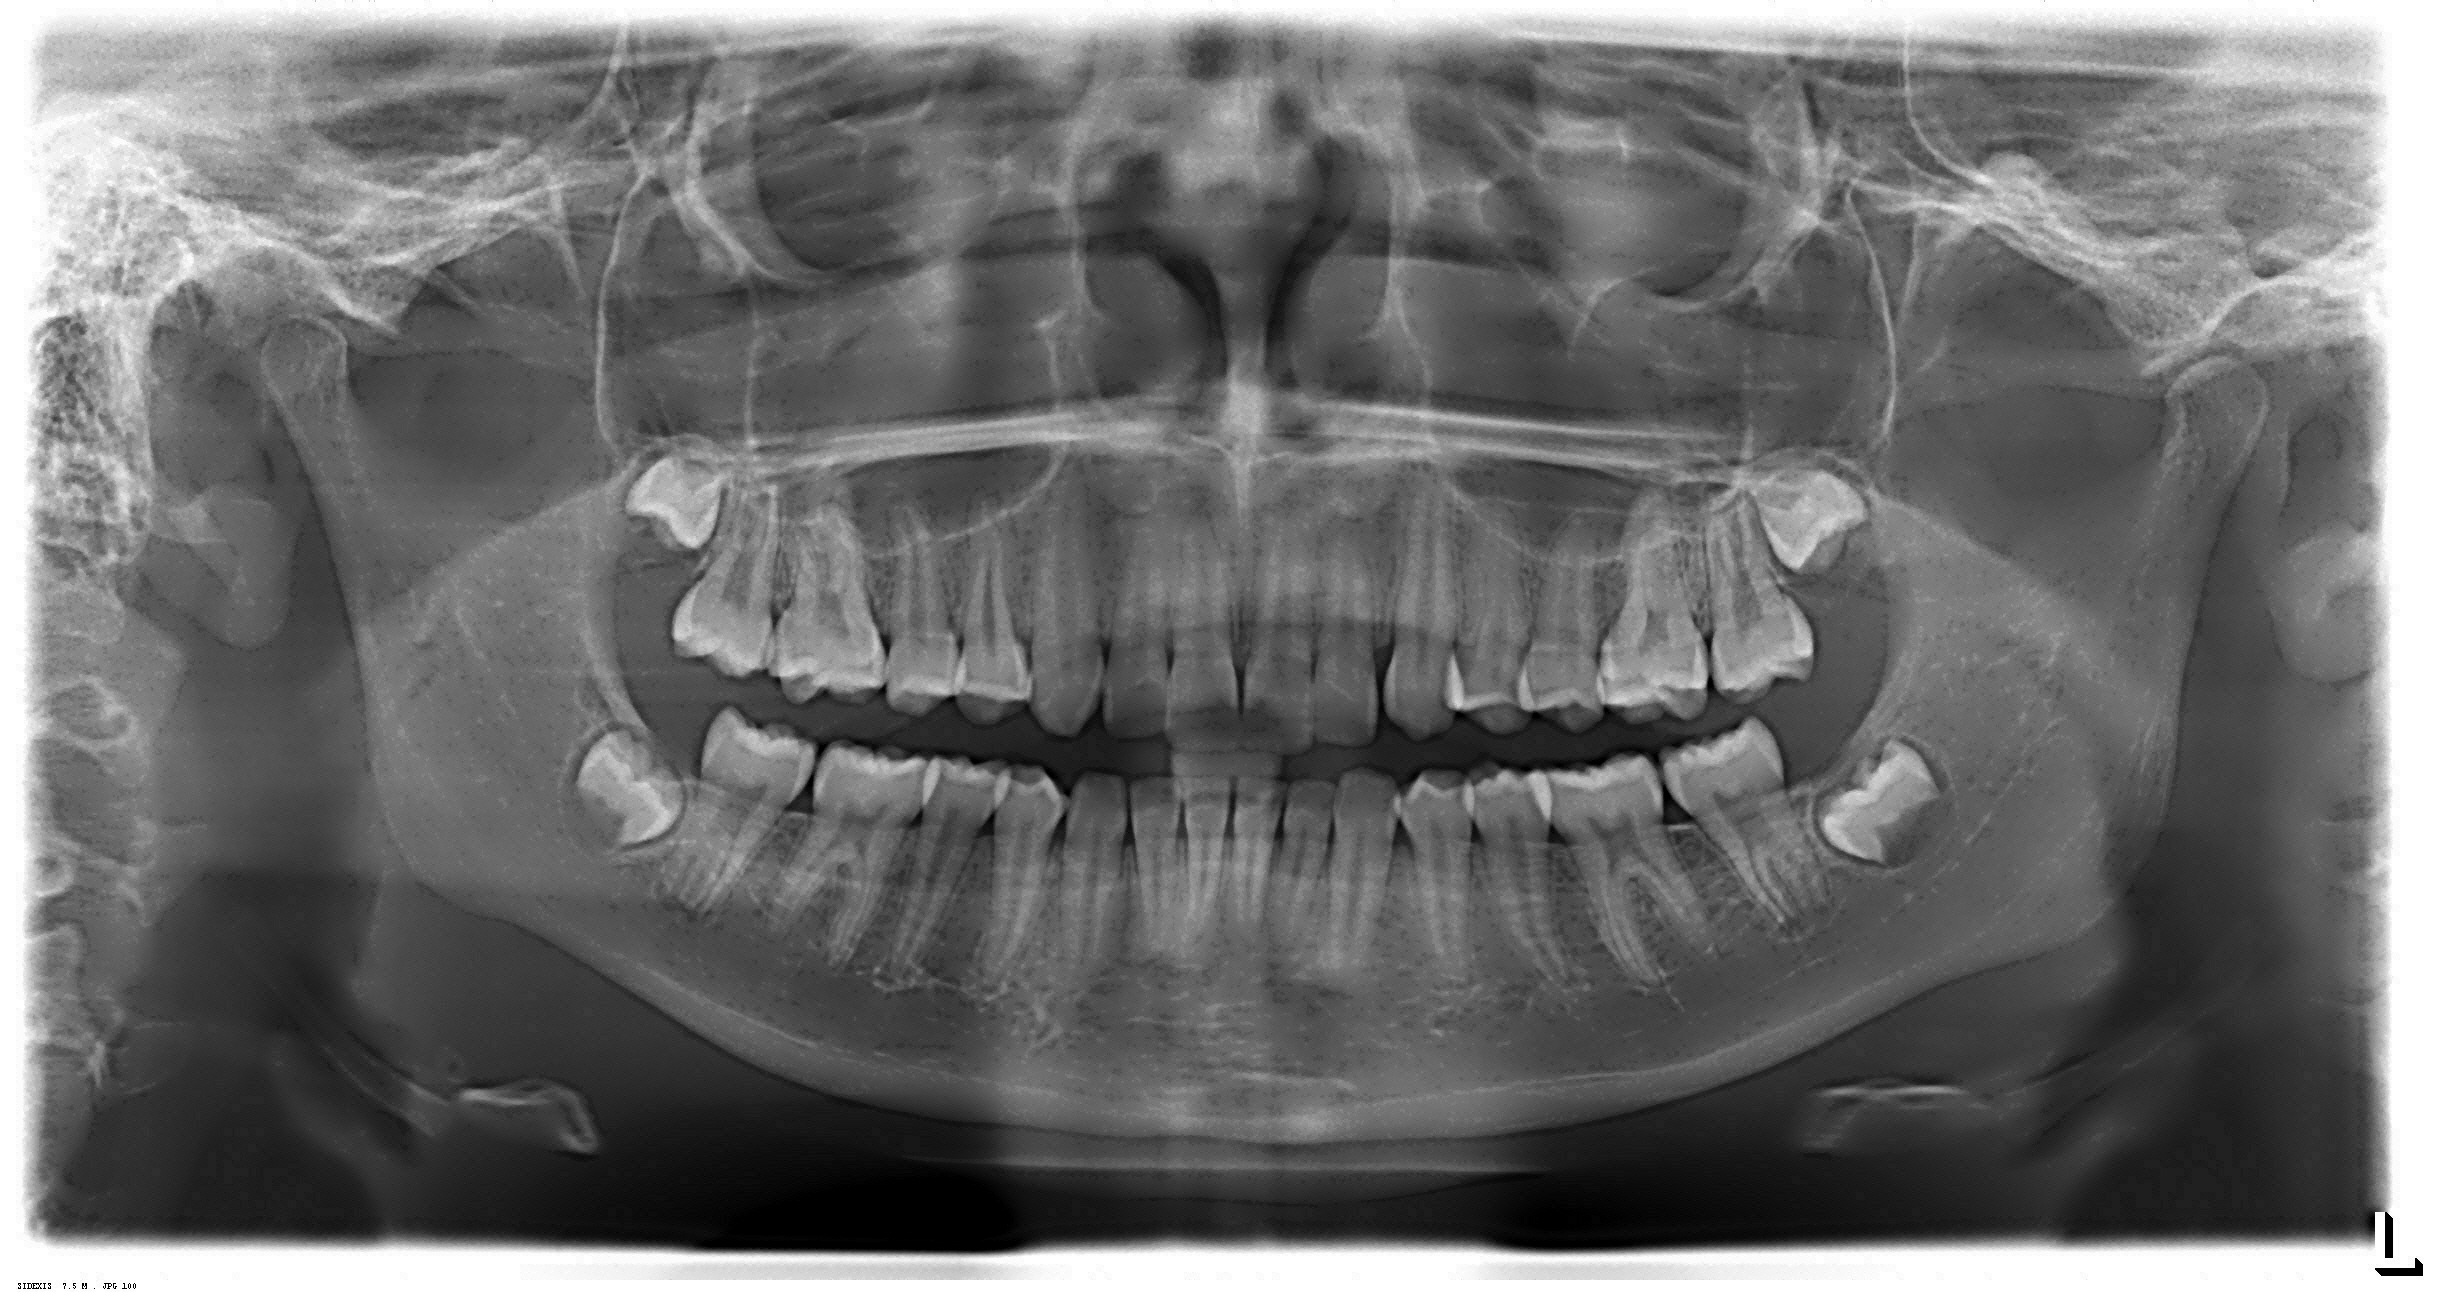

Radiografias Digitais

- Raio X Panorâmico

Documentações